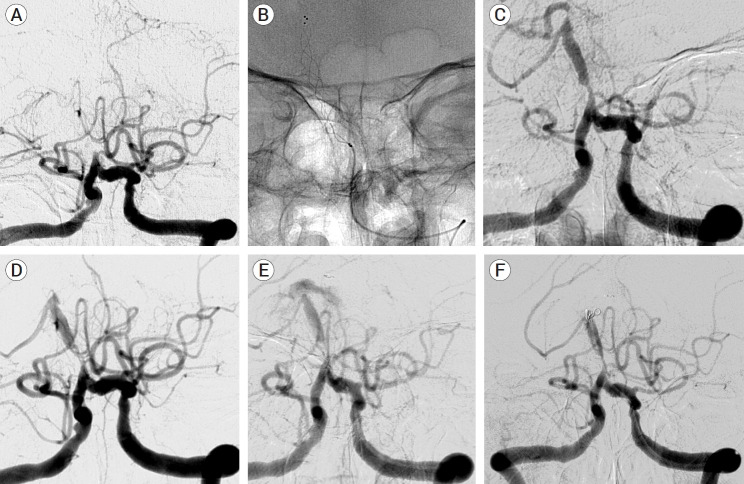

Results: Compared to those without rescue procedures, RAS group had a higher percentage of large artery atherosclerosis as an etiology (p<0.001), long segment occlusions (p=0.03), and was more likely to involve posterior inferior cerebellar artery (p=0.007). There was no difference in functional outcome at 6 months between these two groups. Reopening could not achieve (N=2, 13.3%) and procedural complication rate (iatrogenic rupture) is 6.7% in RAS group. Rescue procedures were complicated with dissection, plaque rupture and migration, device damage, and misplacement of the balloon/stent. Avoiding these traps, finding true lumen, and reconstructing the flow by connecting the proximal and distal normal were the keys to the successful RAS.

Conclusions: RAS could be inevitable during endovascular treatment for PCIS and being aware of possible events and technical strategies would navigate interventionists to successful recanalization and the better outcomes.